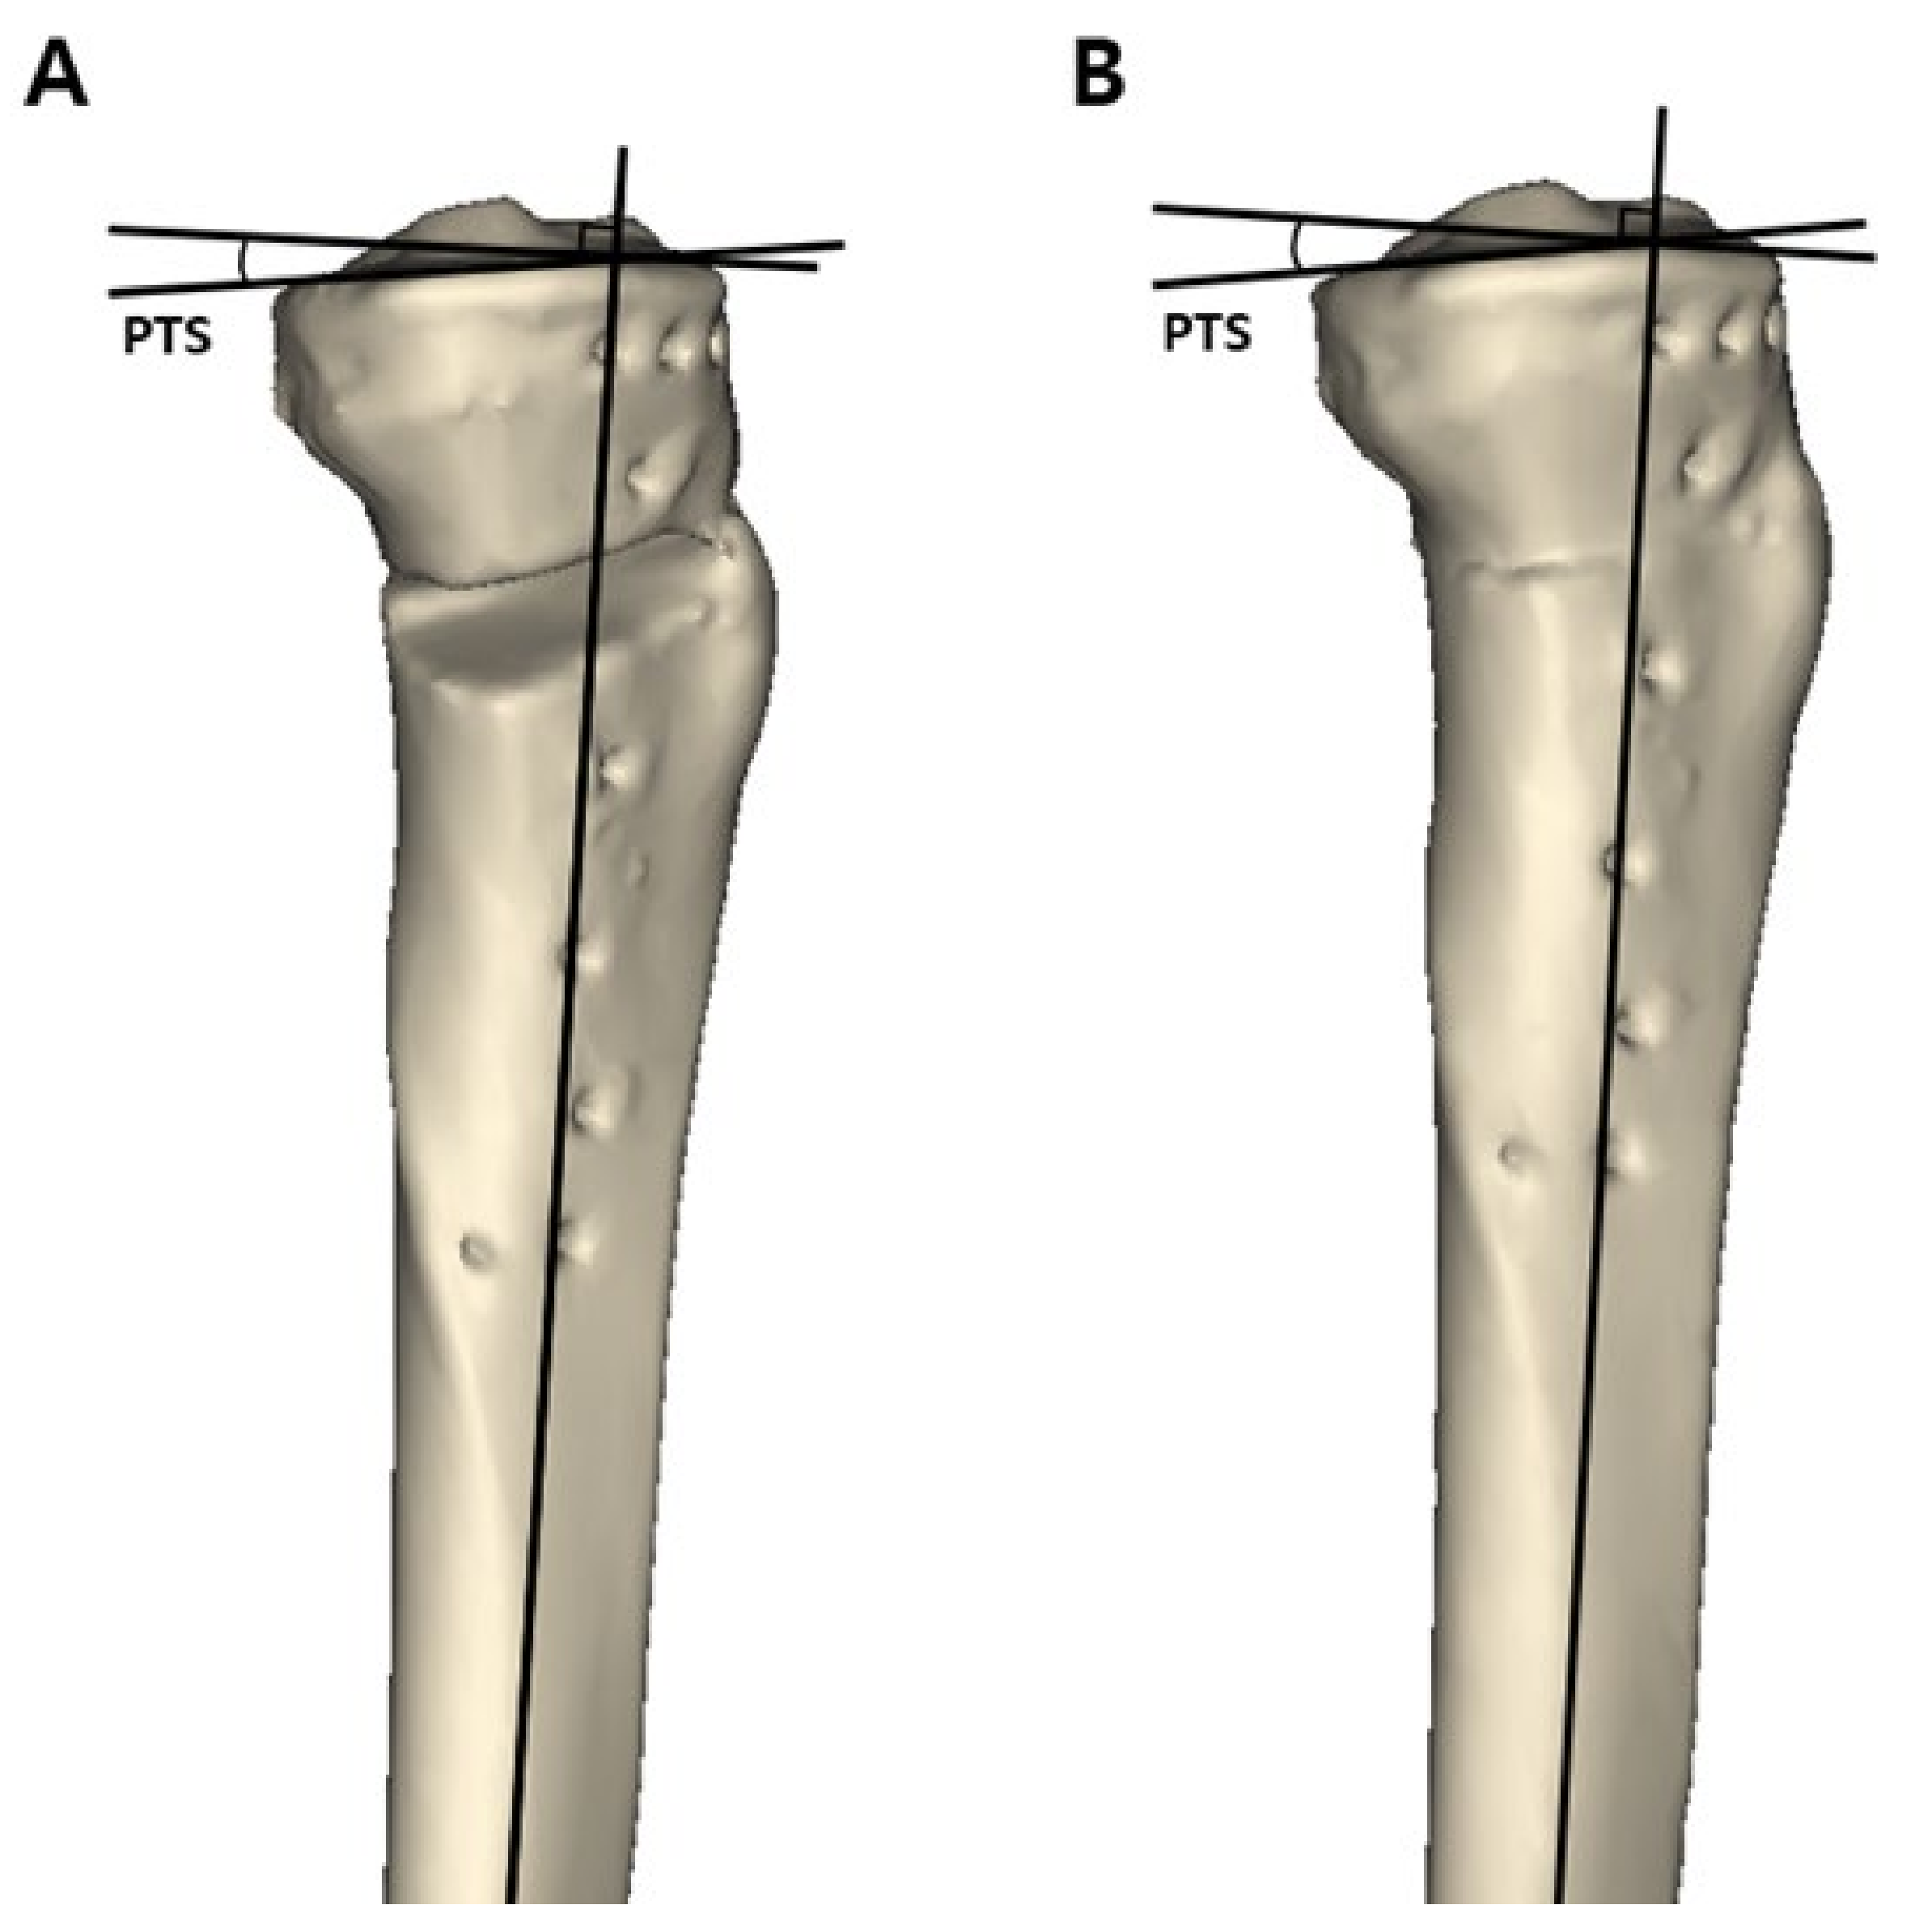

After approval by the institutional review board of our institution, patients with medial compartment osteoarthritis who underwent MOWHTO between May 2011 and November 2017 were retrospectively reviewed. A total of 169 knees were treated with MOWHTO during the study period. Patients who met the following criteria, including the surgical indications of MOWHTO, were included in the study: (1) symptomatic medial compartment osteoarthritis with Kellgren-Lawrence grade III or more, (2) varus deformity of the lower extremity >5°, (3) preserved cartilage in the lateral compartment (International Cartilage Repair Society [ICRS] grade [20] I or II), and (4) age of <65 years. Patients with the following criteria were excluded from the study: (1) patients who did not have a postoperative computed tomography (CT) scan for the full length of the tibia and reconstructed 3D model; (2) a history of previous surgery on the affected knee; and (3) the presence of ligament injury on the affected knee. After applying the inclusion and exclusion criteria, 80 knees were included in this study. The patients were divided into two groups according to the osteotomy inclination angle in the sagittal plane in the 3D model reconstructed CT scan images. When the osteotomy line was inclined anteriorly with respect to the medial tibial plateau line, the cases were classified into group A (Figure 1A), while when the osteotomy line was inclined posteriorly with respect to the medial tibial plateau line, the cases were classified into group P (Figure 1B). Group A and group P consisted of 58 and 22 patients, respectively.

Figure 1. The patients were divided into two groups according to the osteotomy inclination angle in the sagittal plane in a three-dimensional reconstructed model. On the true lateral view, a black dotted line was drawn as a medial tibial plateau line. A black solid line was drawn as a sagittal osteotomy line on the anteromedial aspect of the lowermost part of the proximal tibial segment. The angle (α°) formed by these two lines was defined as the osteotomy inclination angle. (A) Group A, the osteotomy line is inclined anteriorly with respect to the medial tibial plateau line. (B) Group P, the osteotomy line is inclined posteriorly with respect to the medial tibial plateau line.

Figure 2. Measurement of the posterior tibial slope in a three-dimensional reconstructed model. The line perpendicular to the bisecting line of the tibial shaft and medial tibial plateau line was drawn on a true lateral view. The angle formed by these two lines was defined as the posterior tibial slope. (A) Postoperative posterior tibial slope. (B) Preoperative posterior tibial slope measured in the restored original preoperative tibia model. posterior tibial slope = posterior tibial slope.